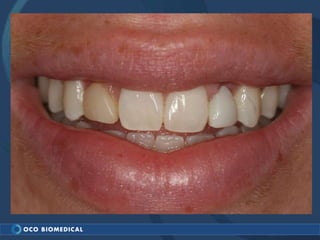

A 3.0mm dental implant was placed to replace congenitally missing maxillary lateral incisors. Dr. Tim Kosinski used a 1.8mm pilot bur and tissue punch to prepare the osteotomy site, then placed the implant by hand and seated it with a torque wrench. After ensuring the implant trajectory was within the restorative envelope, an acrylic coping was placed for temporary fabrication. At the 1 week post-op appointment, excellent soft tissue response and papilla formation were observed, and a final impression was taken to send to the lab for crown fabrication.